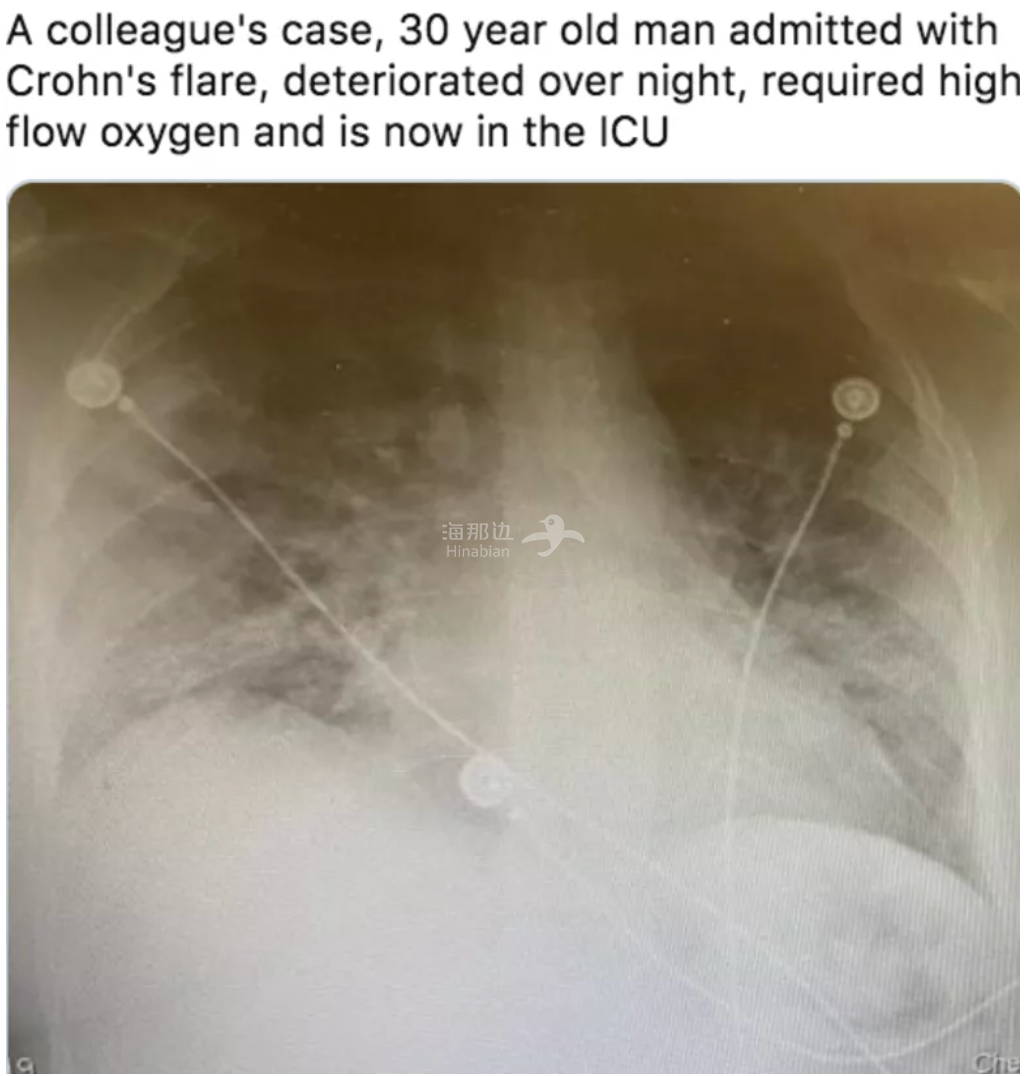

这也让人想到前不久一位加拿大医生分享的30岁患者胸透照片,同样是毫无病史的青年,那位患者的肺部也已经白茫茫一片,严重到需要高流量吸氧,在重症监护室进行急救!